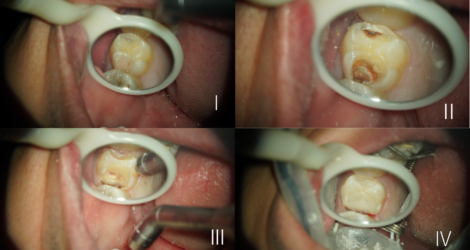

└6CR築造

TC前田です🐰💕

今日は└6CR築造の症例をご紹介します。

前にもCR築造について書きましたが、CR築造とは虫歯が深く神経に近い時に行う治療です。

CR(コンポジットレジン)を使って大きく削られた箇所を修復します。

また、CRを流す前にレーザー治療を行うこともあります。

前回ご紹介したのは└4の小臼歯でしたが、今回は└6の大臼歯のCR築造に …

TC前田です🐰💕

今日は└6CR築造の症例をご紹介します。

前にもCR築造について書きましたが、CR築造とは虫歯が深く神経に近い時に行う治療です。

CR(コンポジットレジン)を使って大きく削られた箇所を修復します。

また、CRを流す前にレーザー治療を行うこともあります。

前回ご紹介したのは└4の小臼歯でしたが、今回は└6の大臼歯のCR築造に …